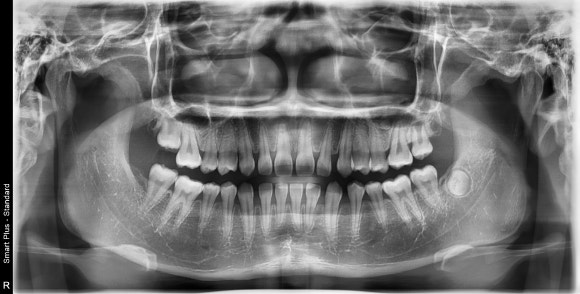

X-ray 촬영,

3D 구강 스캔,

측모 두부 계측 분석 등을 통해 발치가 필요한지를 판단하게 됩니다.